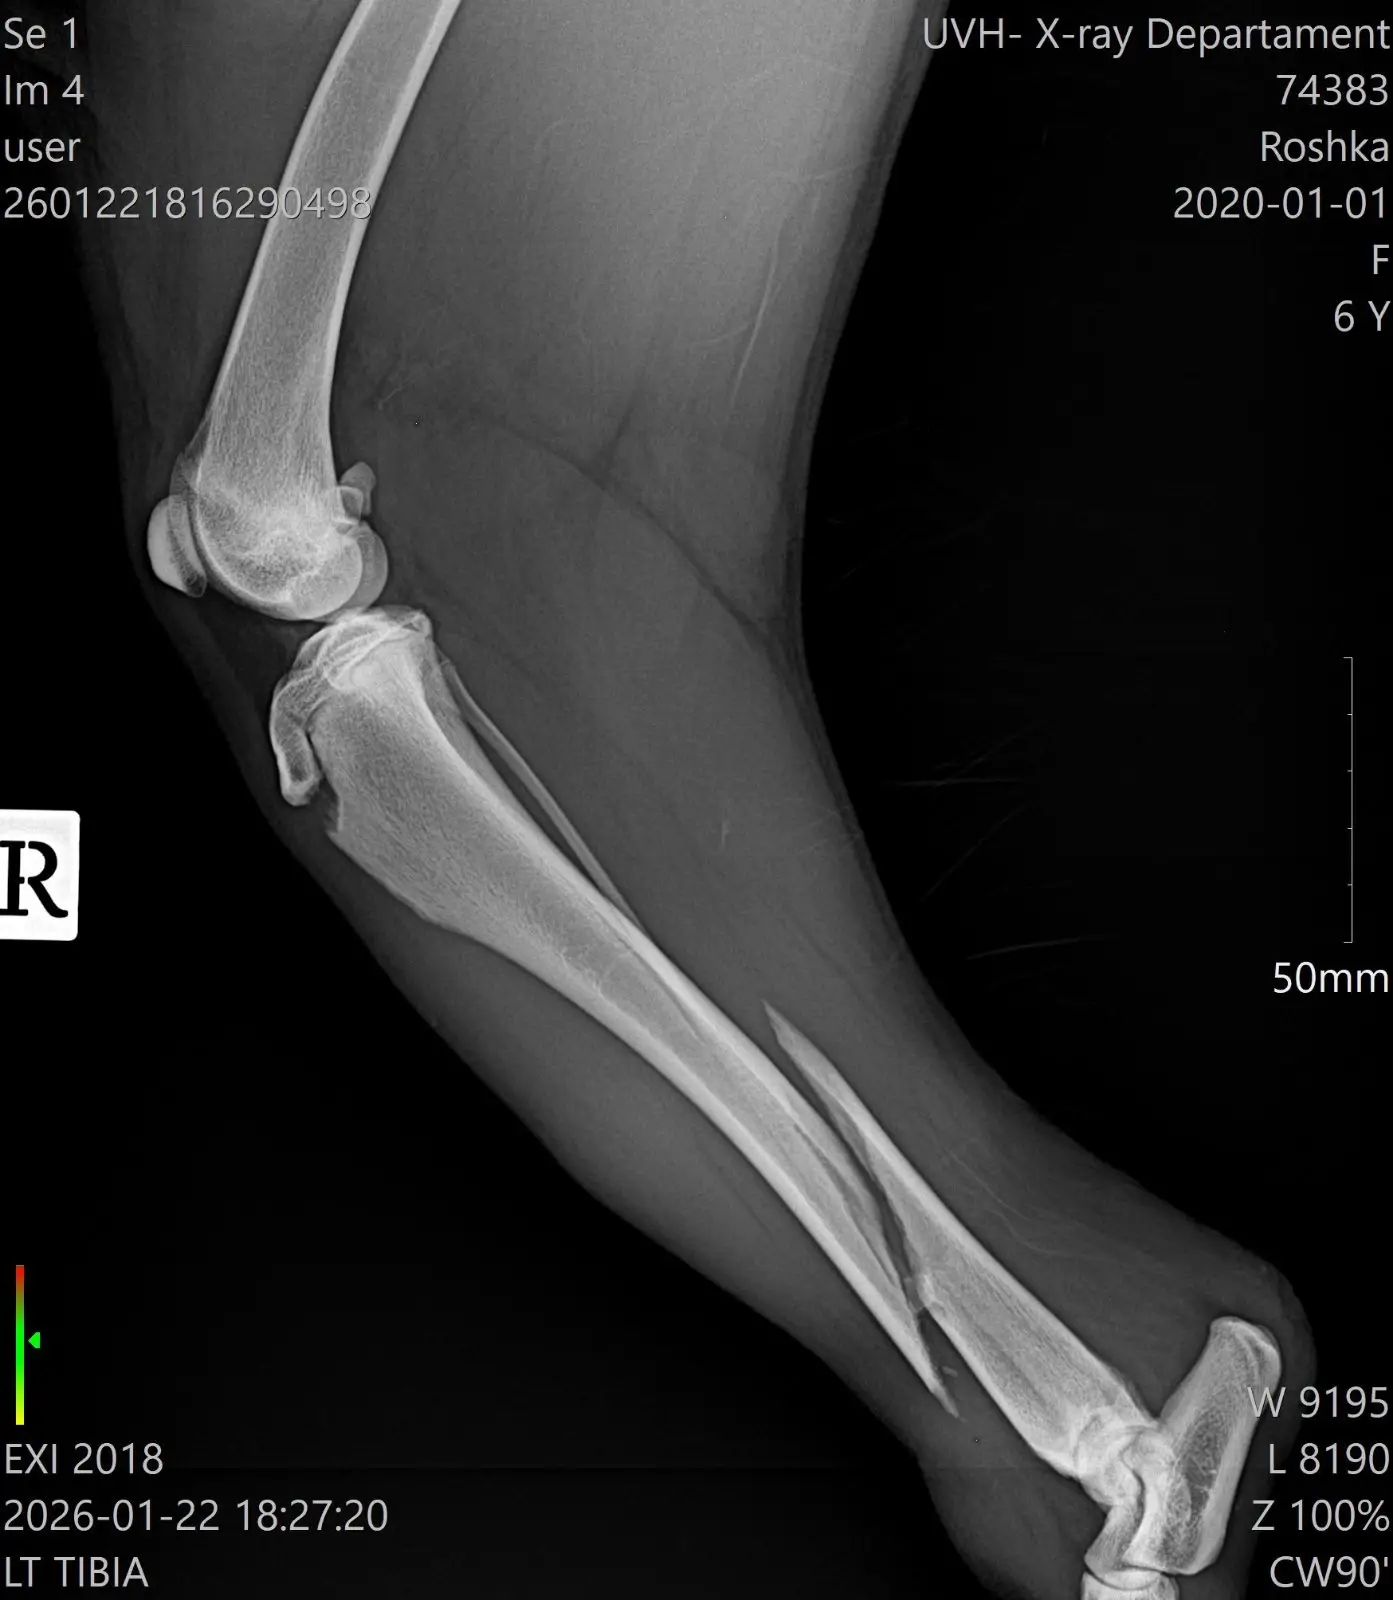

Защо Рошка има нужда от вас

Въпреки силата си, тя не може да се справи сама. Рошка се нуждае от спешни операции на задните краченца. За да може това 25-килограмово тяло да се изправи отново, са необходими импланти и винтове.